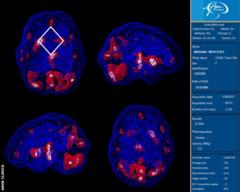

“I ended up going to a clinic in California and they did Spect (single-photon emission computed tomography) scans to see what was really going on inside my brain – which parts were active and which were asleep,” she says.